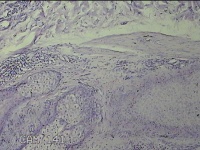

后颈部皮肤结节

性别

男

年龄

45岁

临床诊断

皮肤结节病

发现后颈部皮肤结节半年余。

标本名称

大体所见

灰白粉红色组织1.7x0.9x0.3cm一块,表面带梭形皮肤1.7x0.9cm,皮下见结节1.5x1.1cm一个,切开结节呈实性,切面灰白粉红色,质软。

图2